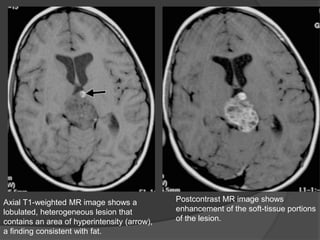

T1-weighted MR images may show foci of T1 shortening due to fat and variable signal

intensity related to calcification.

On T2-weighted images, the soft-tissue component is iso- to hypointense. The soft-

tissue component demonstrates enhancement on postcontrast images. The malignant

form may have a more homogeneous imaging appearance (fewer cysts and

calcifications).

Axial T1-weighted MR image shows a

lobulated, heterogeneous lesion that

contains an area of hyperintensity (arrow),

a finding consistent with fat.

Postcontrast MR image shows

enhancement of the soft-tissue portions

of the lesion.